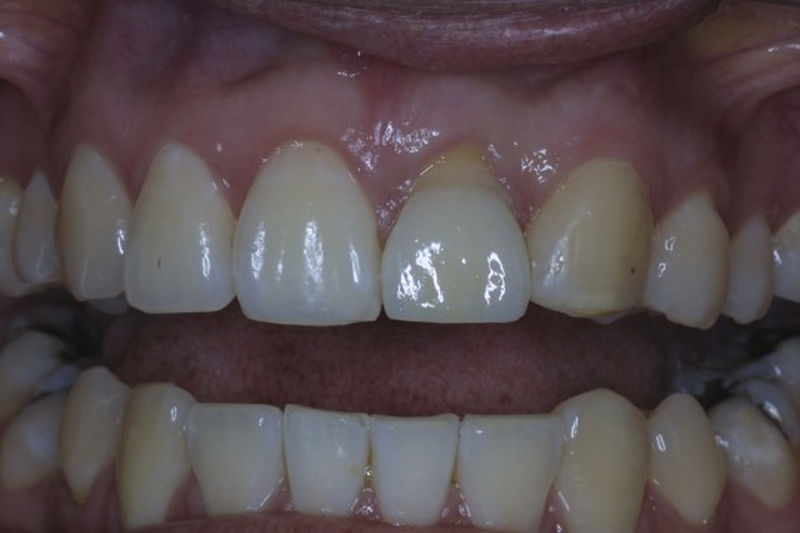

Ortodoncia y coronas.